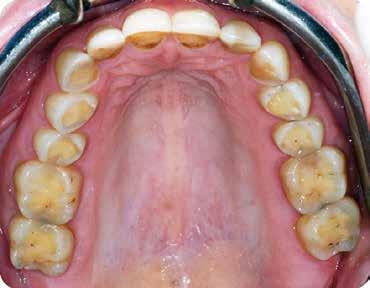

A vizsgálat során a jobb felső első kisőrlőfog (1,4) és a bal felső első kisőrlőfog (2.4), valamint a köztük elhelyezkedő fogak kifejezett mértékű kopását észleltük (14-24). Ezen felül a felső metszőfogak (1.2–2.2) élei egyenetlen lefutással rendelkeztek, és a jobb felső nagymetszőfog (11) – amelyet korábban gyökérkezeltek és kompozit töméssel láttak el –jelentős színbeli eltérést mutatott. Az 1.4-es és 2.4-es fo-

Ezt követően 6 hónapot vártunk a parodontális szövetek gyógyulásának érdekében. Ekkor a mock-up-ot felhelyeztük a páciens fogaira. Mivel a páciens elégedett volt a bemutatott látvánnyal, ezért a kezelés következő fázisának megkezdése mellett döntöttünk. A preparálás előtt a fogak felszínén mélységjelölő barázdákat alakítottunk ki (LVS1 FG Medium Depth Cutting Diamond 834.31.021, Brasseler Dental, One Brasseler Boulevard Savannah, Georgia 31419, Egyesült Államok). A megfelelő anyagvastagság biztosításához ezen felül egy 0,5 mm vastagságú átlátszó redukciós sablont (Keystone Industries, 480 South Democrat Road, Gibbstown, New Jersey, Egyesült Államok) is készítettünk. A sablont egy vákuumkészülék (Pro-Vac Machine 110V, Keystone Industries) segítségével hoztuk létre. A protetikai fázis során a frontfogak és az első kisőrlőfogak kerámia héjakkal történő ellátását terveztük. A preparálás mélységét a sablon felhelyezését követően, a sablonon lévő perforációk segítségével tudtuk ellenőrizni. A nyílásokba parodontális szondát vezettünk, hogy meghatározzuk a redukció mértékét (6. ábra). A preparálás megfelelőségét ezen felül egy gyúrható szilikonból készült sablonnal is ellenőriztük. Ebben az esetben is parodontális szondát használtunk a mélység ellenőrzése céljából (6. ábra). A csonkelőkészítés utolsó lépéseként a lecsiszolt fogfelszíneket polírkorongok segítségével (OptiDisc, Kerr, Orange, Kalifornia, Egyesült Államok) simára políroztuk. A lenyomatvétel során duplafonalas lenyomatvételi technikát alkalmaztunk. Az ínybarázdákba először #00-

ás, majd #0-ás retrakciós fonalakat (Ultrapak, Ultradent Products Inc, South Jordan, Utah, Egyesült Államok) helyeztünk. A végső precíziós lenyomatot polivinil-sziloxán lenyomatanyaggal (Virtual 380, Ivoclar Vivadent AG, Schaan, Liechtenstein) vettük. A fogtechnikai fázisban ultravékony (0,5 mm-nél vékonyabb) földpátkerámia héjak elkészítését kértük (Super Porcelain Ex-3, Kuraray Noritake Dental, Tokió, Japán), (7. ábra). A kerámia héjak készre vitelét követően a próba során a héjakat a helyükre illesztettük a széli zárást, az így kialakított fogformák ellenőrzése céljából. A páciens elégedett volt az így kapott látvánnyal. A végleges ragasztás kofferdám izolálásban történt. A preparált fogak felületét először 37%-os foszforsavval (Total Etch, Ivoclar Vivadent) 15 másodpercen keresztül kondicionáltuk, majd vízzel leöblítettük (8. ábra). A kondicionált zománcfelszíneket Adhese Universal (Ivoclar Vivadent) adhezívvel kezeltük. A kerámiahéjak homorú felszíneit 5%-os folysavval (IPS Ceramic Etching Gel, Ivoclar Vivadent) 20 másodpercen át kondicionáltuk, majd a felszíneket Monobond Plus primerrel (Ivoclar Vivadent) vontuk be (7. és 8. ábrák). A héjakat fényre kötő rezinalapú ragasztócement (Variolink Esthetic LC, Ivoclar Vivadent) applikálását követően a helyükre illesztettük. A kifolyó cementfelesleg eltávolítását követően minden felszínt (labiális, palatinális, meziális és distális) LED-es polimerizációs lámpával (VALO Cordless, Ultradent) 40 másodpercen keresztül megvilágítottuk.

A páciens elégedett volt a végleges restaurátumok színével, formájával és méretével. A kezelés végeredménye kielégítette az esztétikai elvárásait (9. ábra). A frissen átadott restaurátumok épségének megőrzése érdekében a páciens számára éjszakai fogvédősínt készítettünk. A páciensünk a négyéves kontrollvizsgálat során is nagyon elégedett volt a kezelés eredményével. A korábban meglévő fekete háromszögek eltűnésének különösképpen örült (9. és 10. ábrák)